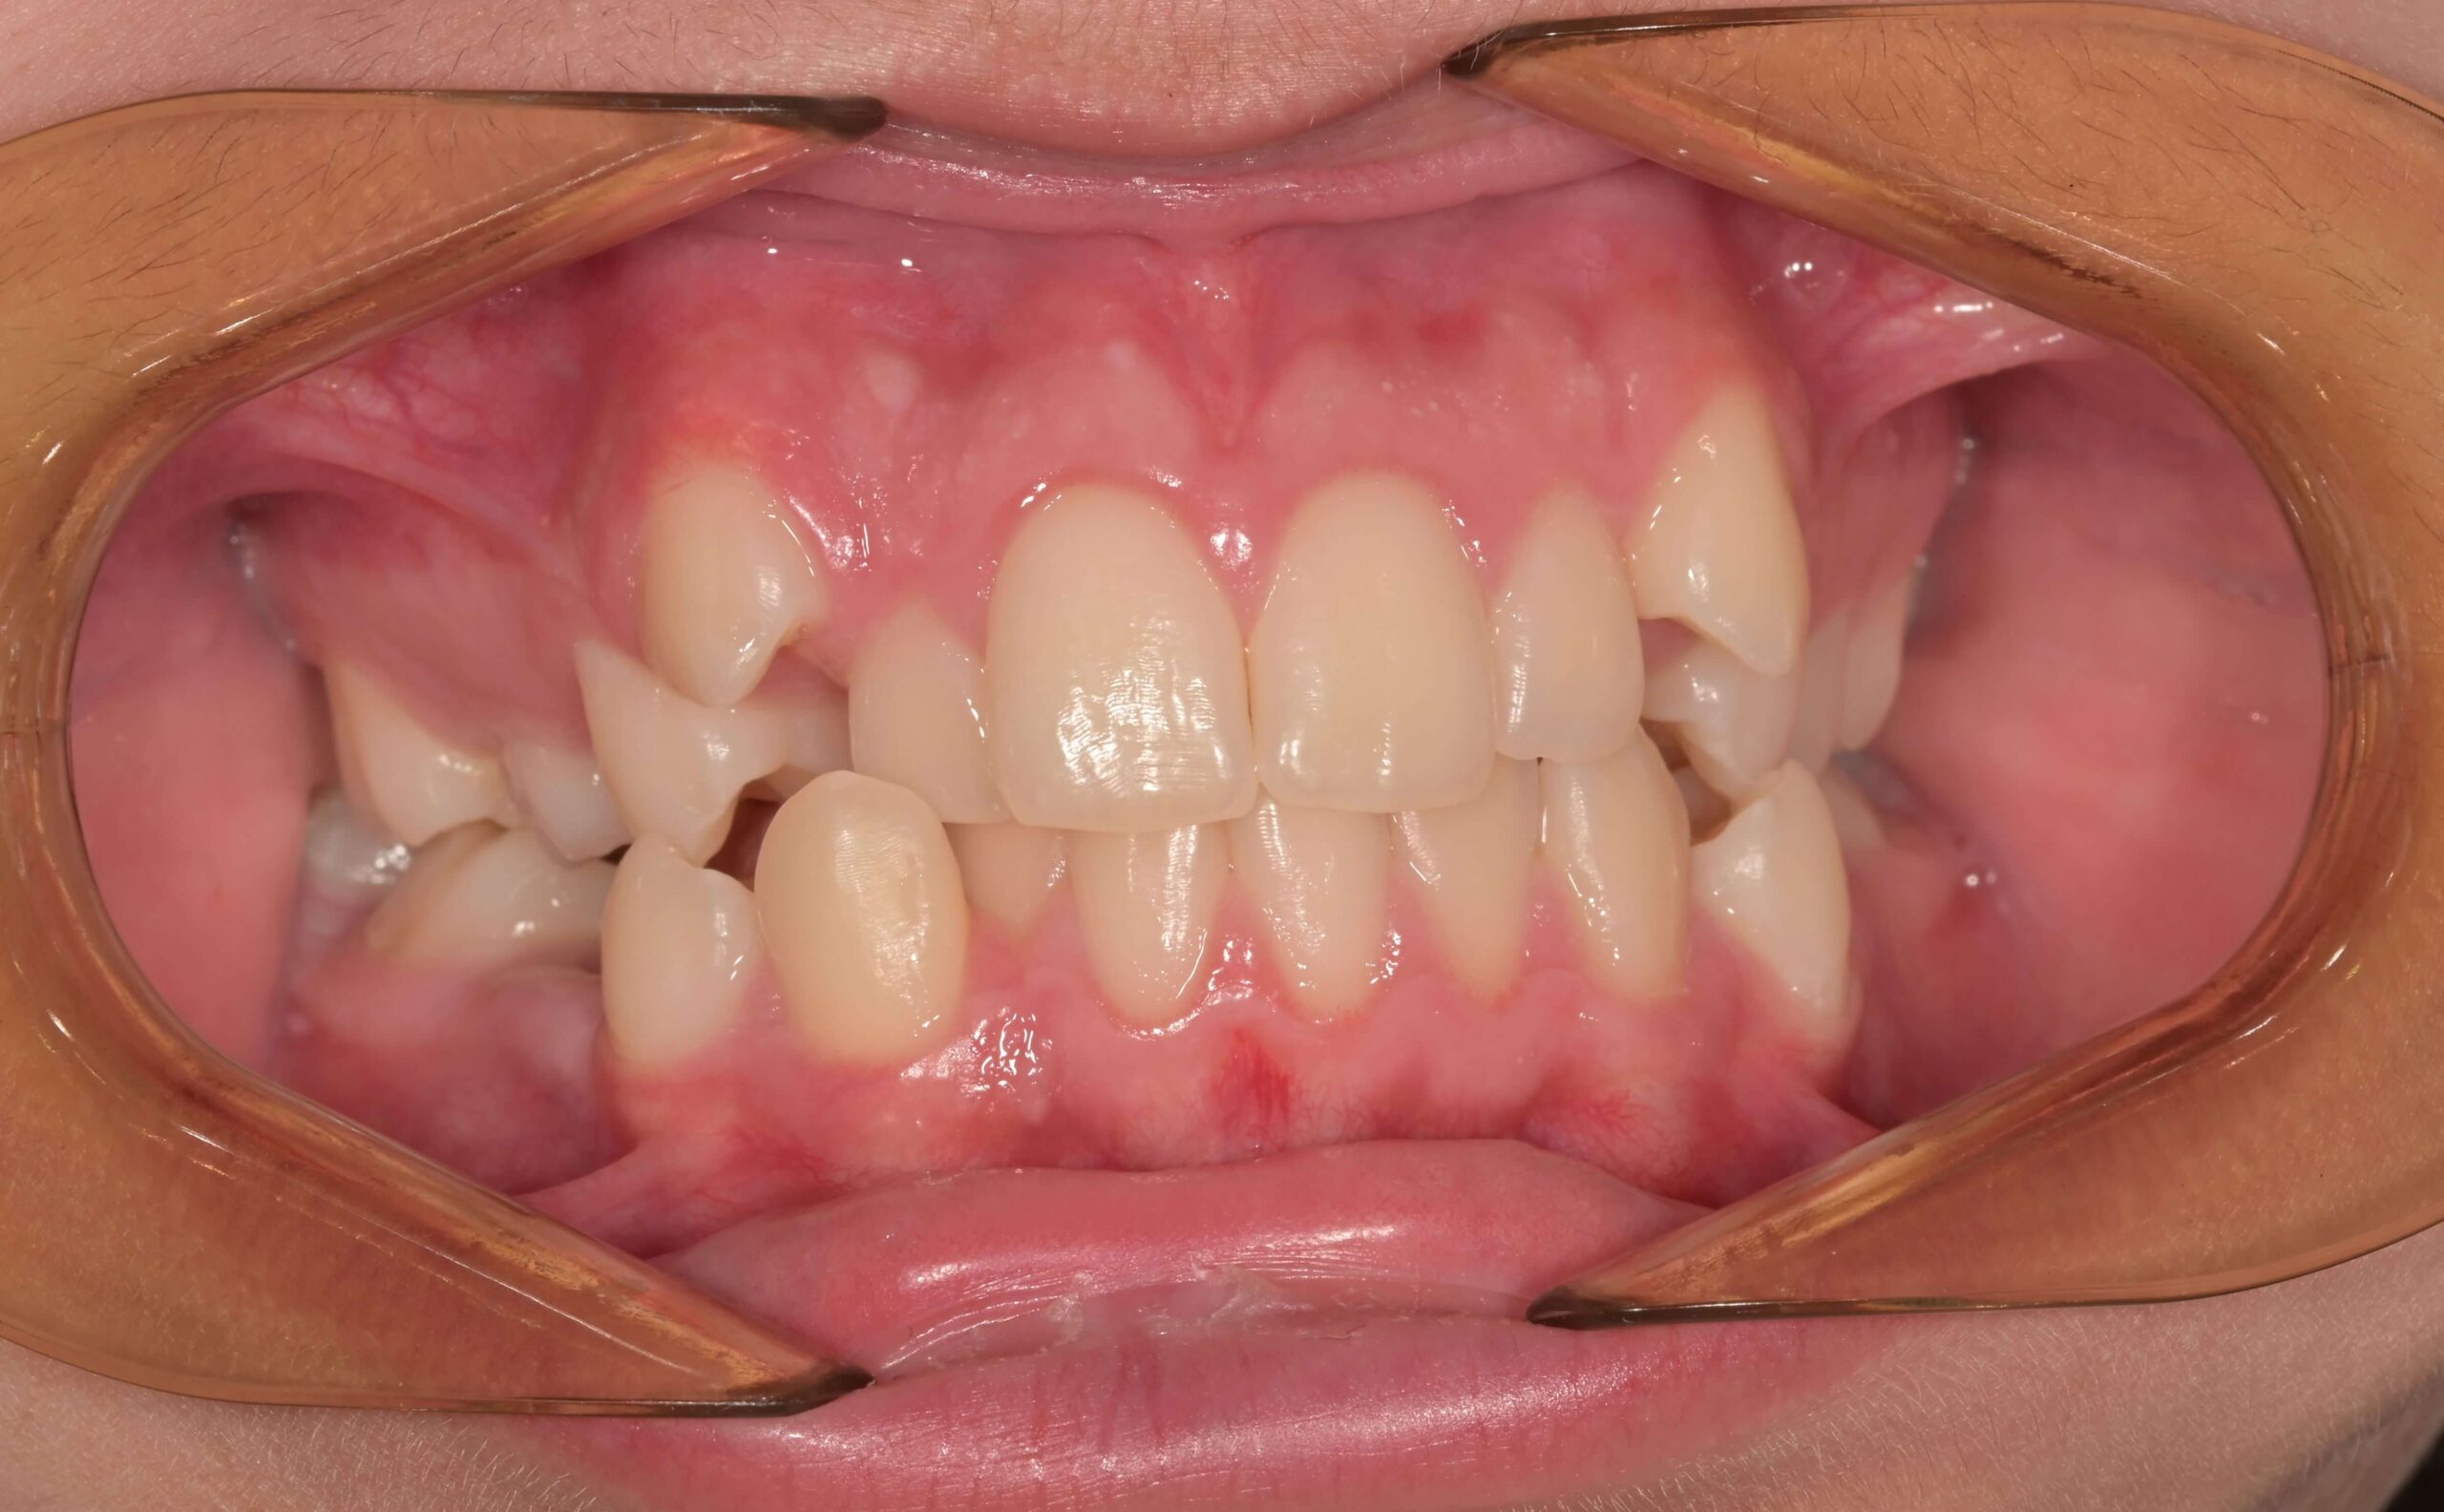

Кръстосаната захапка е една от най-често срещаните форми на малоклузия (неправилно подреждане на зъбите), при която горни зъби захапват вътре спрямо долните, вместо да ги покриват отвън, както е при нормална оклузия. Тази зъбна аномалия може да засегне единичен зъб или група зъби, засягайки предната или задната част на устата.

Кръстосаната захапка се получава, когато горната челюст е компресирана (стеснена), докато долната продължава да се развива и няма какво да я спре. Това води до несъответствие между горната и долната редица зъби.

Предна кръстосана захапка – при нея горните предни зъби застават зад долните предни зъби.

Задна кръстосана захапка – горните кътници захапват от вътрешна страна спрямо долните кътници. Задната кръстосана захапка може да бъде едностранна или двустранна.